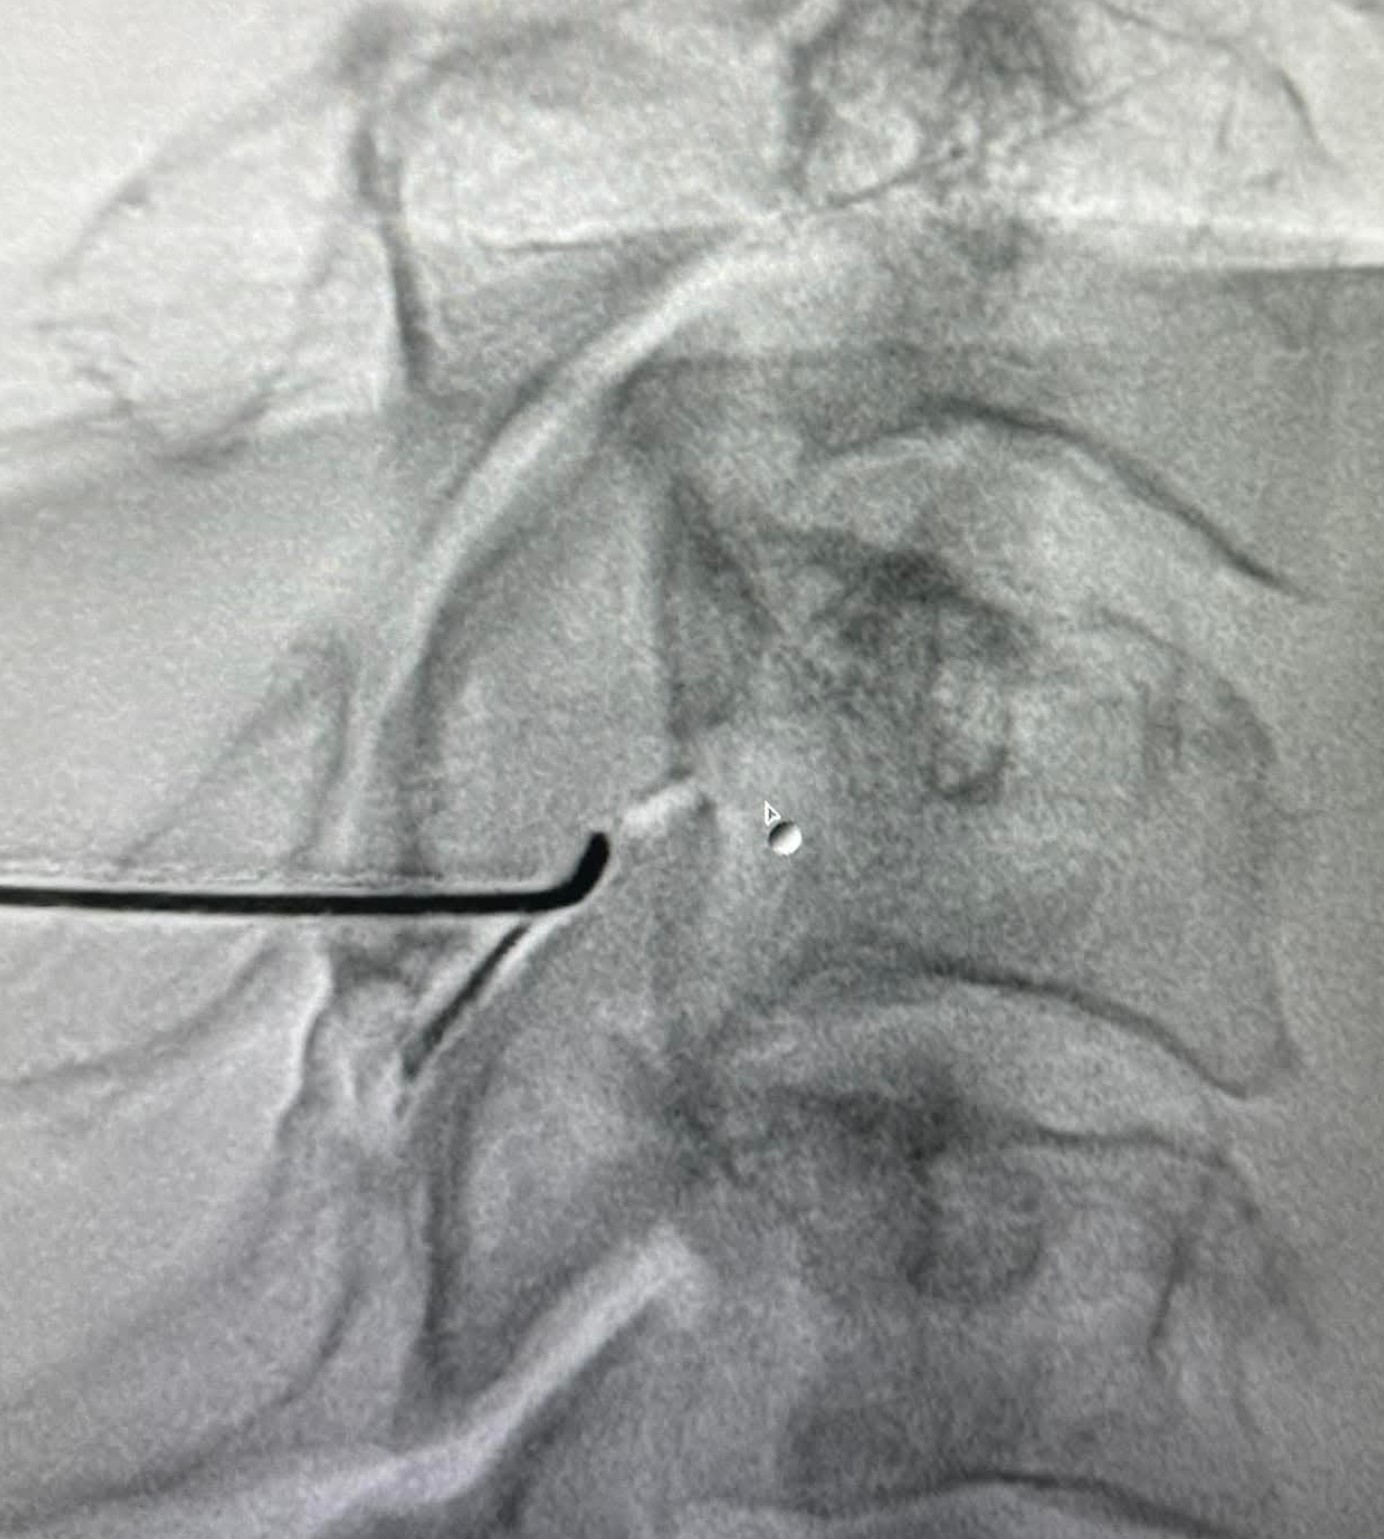

- Επισκληρίδια έγχυση επί υποκείμενης κήλης μεσοσπονδυλίου δίσκου με ή χωρίς ριζιτική προσβολή